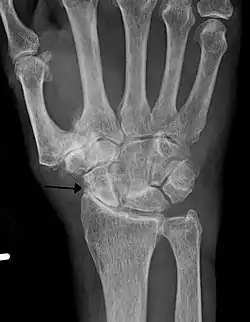

Diagnosis is made with reasonable certainty based on history and clinical examination.[52][53] X-rays may confirm the diagnosis. The typical changes seen on X-ray include: joint space narrowing, subchondral sclerosis (increased bone formation around the joint), subchondral cyst formation, and osteophytes.[54] Plain films may not correlate with the findings on physical examination or with the degree of pain.[55]

Severe osteoarthritis and osteopenia of the carpal joint and 1st carpometacarpal joint -